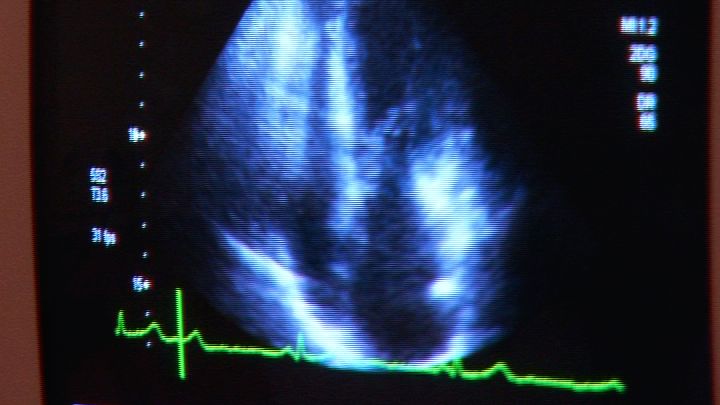

Die Herzinsuffizienz, auch bekannt als Herzschwäche, ist eine schwerwiegende Erkrankung. Um die...